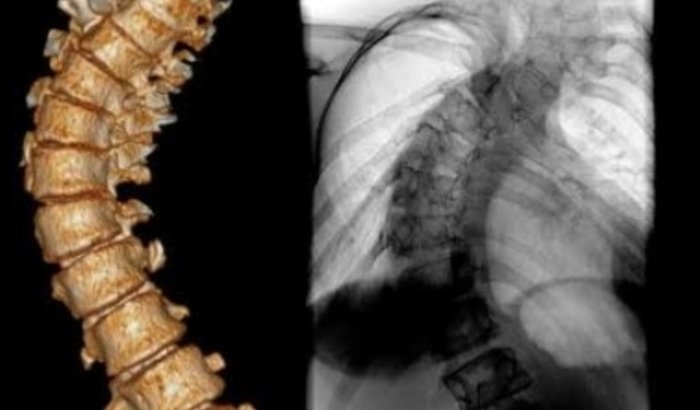

Ajude a Família de Wellington a Superar Desafios Médicos e FinanceirosImagine ter que enfrentar não apenas uma, mas duas cirurgias delicadas na coluna vertebral, aos 15 anos de idade.

Essa foi a realidade do Wellington, diagnosticado com cifoescoliose devido à neurofibromatose tipo I. As cirurgias foram um passo crucial em sua jornada, realizadas no Hospital Sarah Kubitschek, em Brasília, no ano de 1997.Desde então, Wellington tem sido acompanhado de perto pela equipe médica do hospital. No entanto, ao longo dos anos, ele enfrentou novos desafios. Em 2017, aos 34 anos, um AVC mudou completamente sua vida. O diagnóstico revelou um forame oval patente, que permitiu a passagem de um coágulo para seu cérebro, causando o AVC. Após um procedimento de cateterismo em 2018 para fechar o forame, Wellington estava determinado a retomar o tratamento para sua coluna.Infelizmente, a espera por uma nova cirurgia foi prolongada devido à pandemia de COVID-19, interrompendo cirurgias eletivas. Agora, em fevereiro de 2024, Wellington finalmente recebeu a oportunidade tão esperada para realizar a cirurgia na coluna. No entanto, sua batalha está longe de terminar.Morando no interior do Rio de Janeiro, a cirurgia em Brasília representa não apenas um desafio médico, mas também financeiro e logístico. Wellington precisa do apoio de sua esposa, filho e sogra durante esse período difícil. Sua esposa será sua principal cuidadora durante o dia, enquanto sua sogra cuidará do filho do casal, que tem apenas três anos de idade.Com suas economias já esgotadas devido aos altos custos logísticos do tratamento e à perda de renda devido à sua condição de saúde, Wellington enfrenta agora a difícil tarefa de custear a viagem e a estadia de sua família em Brasília. Sem esse apoio, ele teme não ser capaz de passar pela cirurgia com tranquilidade, sabendo que sua família está segura e cuidada ao seu lado.É por isso que estamos lançando esta campanha para ajudar a família de Wellington a superar esses desafios. Cada doação, por menor que seja, fará uma diferença significativa em suas vidas. Vamos mostrar a Wellington e sua família que eles não estão sozinhos nesta jornada. Vamos nos unir como comunidade para oferecer o suporte necessário para que Wellington possa enfrentar sua cirurgia com esperança e coragem.Sua generosidade pode fazer toda a diferença. Junte-se a nós hoje e faça parte desta história de superação!